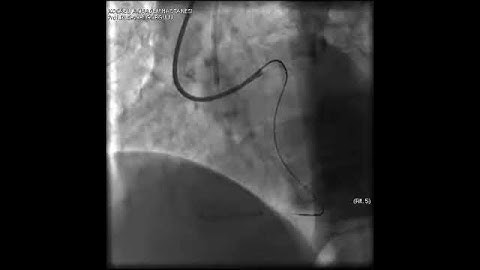

Aortic dissection and radial rupture during retrograde CTO PCI: Management of complications VİDEO 22